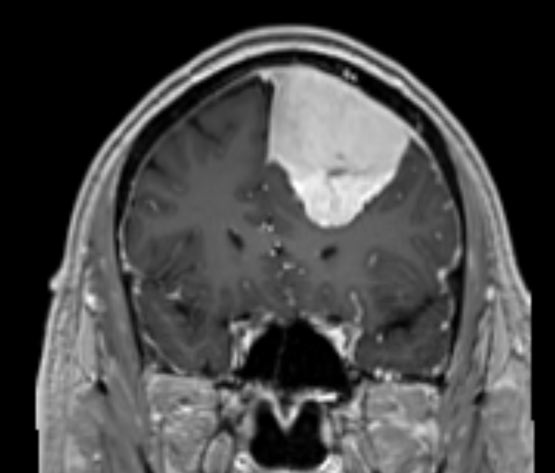

בת 60 עם שינויי התנהגות בשנה האחרונה, אובחנה עם מנינגיומה פארא סגיטלי אשר נותחה להסרה.